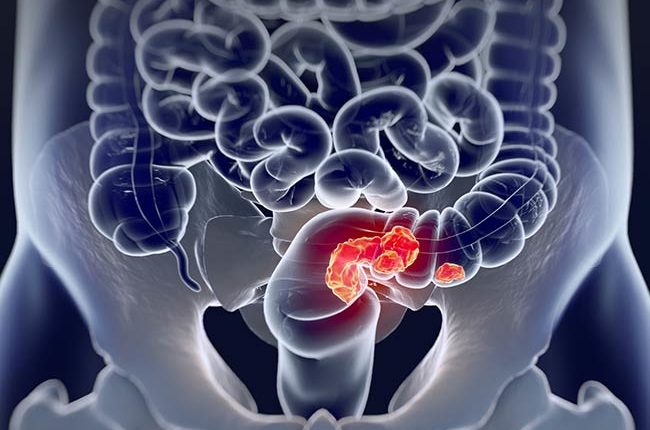

Tijuana, 17 de agosto de 2022.- En la ultima década, el cáncer colorrectal ha tenido un incremento de casos superior a otro tipo de tumores y esto se debe principalmente a dietas pobres en fibra y ricas en proteína

Precisó que este tipo de tumores son el segundo padecimiento más común en hombres y el tercero en mujeres y que aunque existe suficiente información y campañas para su detección oportuna, la población no se realiza revisiones periódicas y quienes si se examinan no concluyen con el ciclo de diagnóstico y tratamiento adecuado por lo que la mayoría de los pacientes comienzan a tratarse en una etapa avanzada.